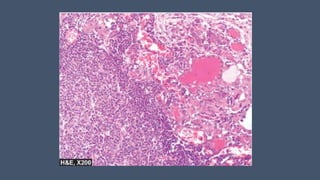

Histopathology of skin lesions in SLE

An H&E-stained section shows liquefactive

degeneration of the basal layer of the epidermis and

edema at the dermoepidermal junction